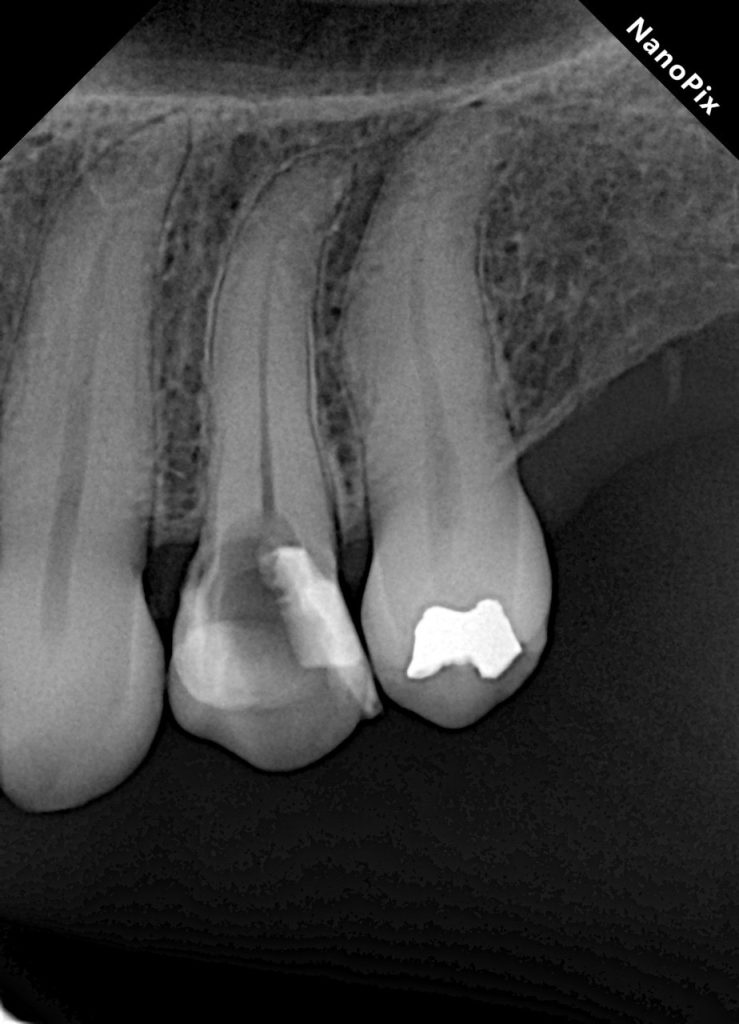

This case demonstrates the complete management of a maxillary premolar with irreversible pulpitis and compromised coronal structure. The treatment involved root canal therapy under rubber dam isolation, followed by adhesive restoration to ensure functional and esthetic rehabilitation.

4. Cleaning & Shaping